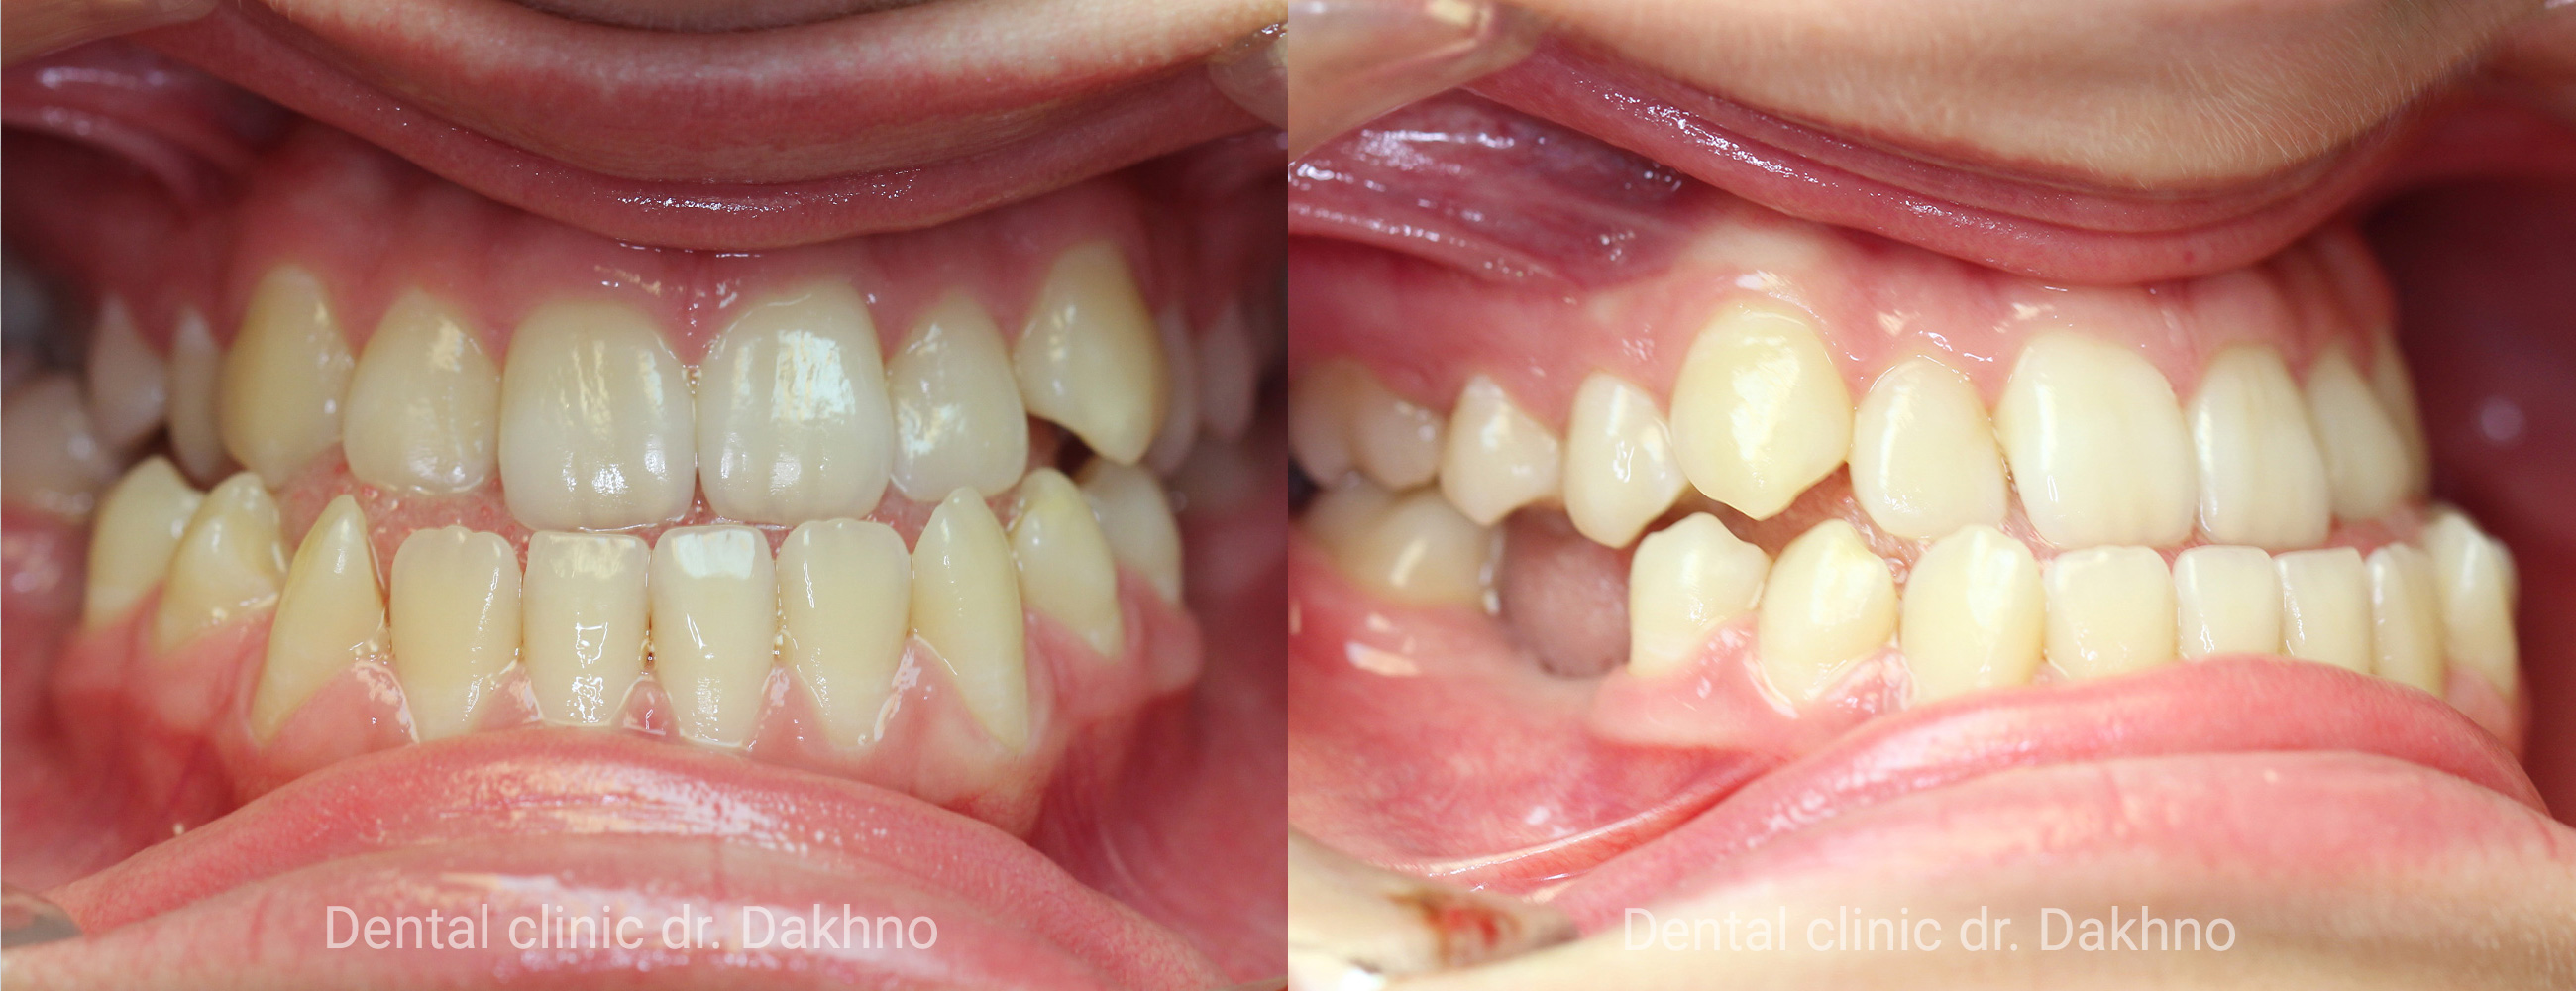

Липень 2017 Діагностичний внутрішньоротовий фотопротокол.

Жовтень 2019 Контрольний фотопротокол. Лікування закінчено. Ретенція зубних рядів забезпечена капами. Незважаючи на складну багатоетапну ортодонтичну апаратуру, яка була використана на етапах ортодонтичного лікування зуби повністю зберегли свій стан і цілісність, завдяки ретельній індивідуальній гігієні і старанням Ксенії.